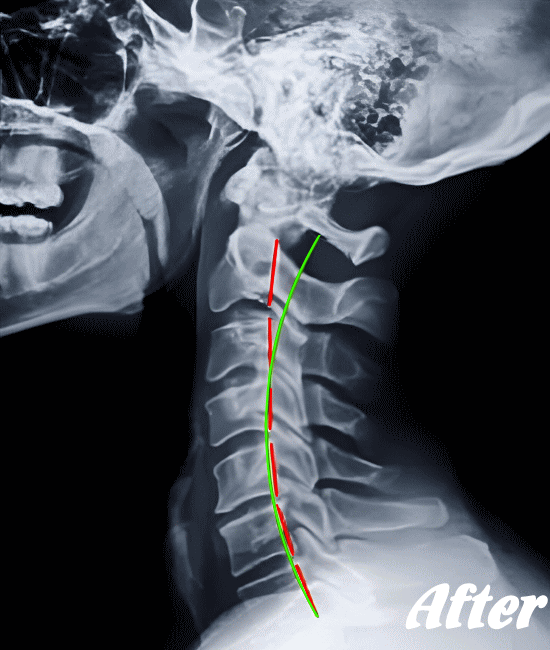

したがって、まずは病院にて検査をお勧めします。検査で問題なければ、骨のズレを調節するための施術を受けてみてはいかがでしょうか。

HALOカイロプラクティック☆平和島整体院では、骨盤(仙腸関節)から背骨(腰椎、胸椎、頸椎)、肋骨(肋椎関節)、肩甲骨(肩甲胸郭関節)などを調整し緩めることで、首(頚椎)にかかる負担を取り除き、可動域を良くして痛みを解消していきます。

首や肩周りの症状では、肩甲胸郭関節(肩甲骨周辺)を調整することは必須です。

寝違えやムチ打ちは、速効矯正・即効施術の【体の整体】の適応になります。